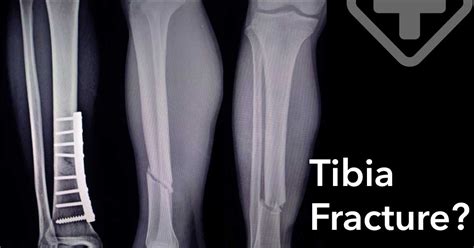

Once you’ve made it to the doctor with a suspected LP tibia fracture , the next crucial step is diagnosis. Doctors are pretty thorough with this, and it usually involves a combination of physical examination and imaging. First up, they’ll conduct a physical examination . This is where they’ll carefully assess your leg, looking for obvious signs of injury. They’ll check for swelling, bruising, and any visible deformities. They’ll gently palpate (feel) the bone to pinpoint the area of maximum tenderness and assess for any instability. They’ll also check your neurovascular status , which is super important. This means they’ll assess nerve function (like sensation and muscle control in your foot and toes) and blood flow (checking for pulses in your foot, skin temperature, and color) to make sure everything is getting enough oxygen and isn’t being compromised by the injury or swelling. If the skin is broken, they’ll assess the wound for contamination and the extent of damage. Following the physical exam, the definitive diagnosis usually comes from imaging. X-rays are the go-to for diagnosing most bone fractures. They’ll take X-rays of your tibia and ankle from different angles to get a clear picture of the fracture. This helps them determine the location, the pattern of the break (is it a clean break, comminuted with multiple fragments, or involving the joint?), and the degree of displacement (how far the bone fragments have moved). In cases of complex fractures, especially those involving the ankle joint (like pilon fractures), or when X-rays don’t provide a complete picture, CT scans (Computed Tomography) might be ordered. CT scans provide more detailed cross-sectional images of the bone and surrounding structures, giving the doctors an even better understanding of the fracture’s complexity, including any damage to the cartilage or small bone fragments. MRI scans (Magnetic Resonance Imaging) are less common for initial fracture diagnosis but might be used later if there’s concern about associated soft tissue injuries, such as ligament tears, tendon damage, or cartilage injuries, which are often present with severe tibia fractures. Once all this information is gathered, the medical team can accurately diagnose the specific type and severity of your LP tibia fracture, paving the way for the right treatment plan.